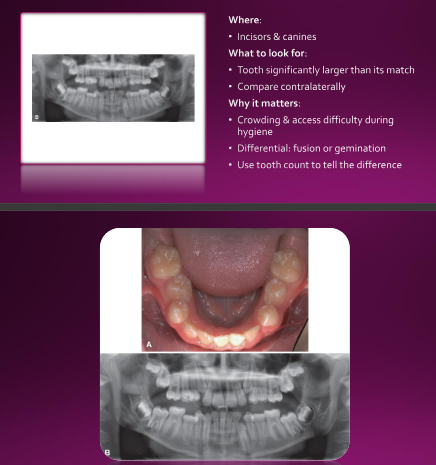

Macrodontia